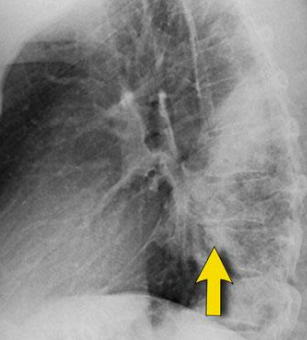

* Nombra el signo * Patrón observado

- Balas de cañón - Nodular

- Patrón - Característico de: - Nombre del signo:

- Nodular - TB activa - **Patitas de rana "árbol en brote"**